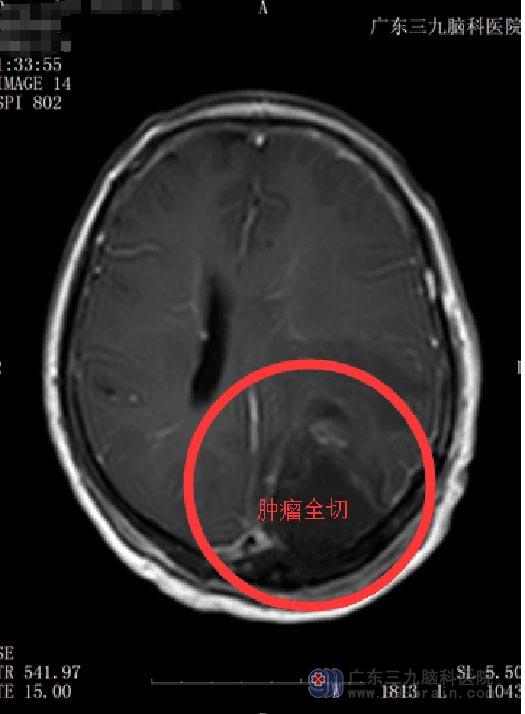

带着一点怀疑,他们来到广东三九脑科医院综合神经外科,再次做了核磁共振检查,鲁明主任将前后检查的片子作了仔细的对比和鉴别,觉得脑膜瘤的可能性更大一些。完善术前检查后,由鲁明主任主刀行左侧顶枕部脑膜瘤切除术,手术十分顺利,术后病理提示:过渡性脑膜瘤,WH0Ⅰ级。

手术后的李阿姨心情很好,身体恢复很快,头痛头晕的症状没有了,视力也恢复了正常。她说:这是老天对我的厚爱。

▲手术后MR